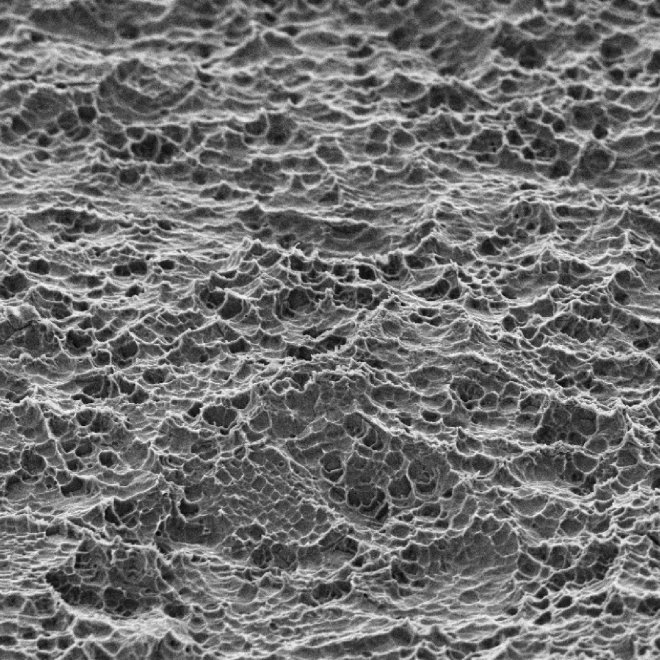

O SUPEX é um tratamento superficial que promove uma área de contato com o osso 100% maior do que os implantes com superfície lisa. Sua superfície rugosa, porém uniforme, é obtida através de um tratamento ácido sequenciado patentead

Esta superfície provê melhores condições de cicatrização e reduz o tempo de osseointegração.

Com esse tratamento conseguimos uma porosidade homogênea [micro e macro porosidade] ideais para a interação entre implante e tecido ósseo.